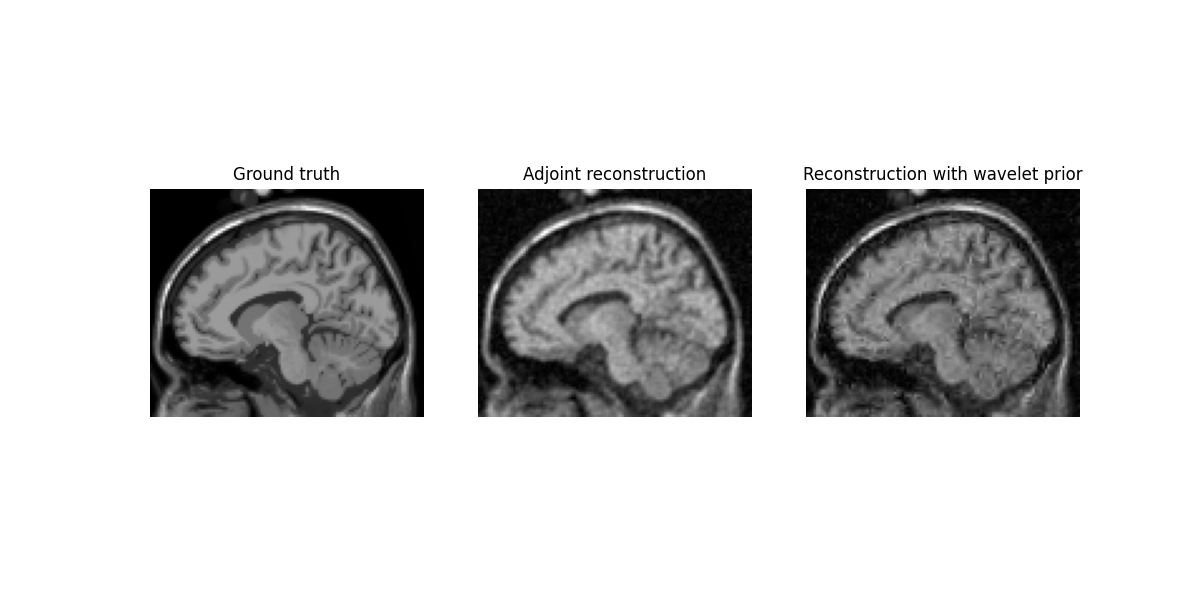

This example demonstrates how to reconstruct image from non-Cartesian k-space data with a regularization prior, using deepinv.

Display results

plt.figure(figsize=(12, 6))

plt.subplot(1, 3, 1)

plt.imshow(torch.abs(mri[..., mri.shape[2] // 2 - 5]).cpu(), cmap="gray")

plt.title("Ground truth")

plt.axis("off")

plt.subplot(1, 3, 2)

plt.imshow(

torch.abs(x_dagger[0, 0, ..., x_dagger.shape[2] // 2 - 5]).cpu(), cmap="gray"

)

plt.title("Adjoint reconstruction")

plt.subplot(1, 3, 3)

torch.abs(x_wavelet[0, 0, ..., x_wavelet.shape[2] // 2 - 5]).cpu(), cmap="gray"

plt.title("Reconstruction with wavelet prior")